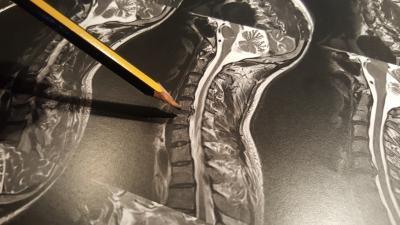

The symptoms of my herniated disc started with numbness in my right thumb, it wasn't until a couple of weeks later that I saw my GP about it, he immediately diagnosed a herniated C5/C6 disc (at the top of teh spine). The nerve that is being comressed by that particular herniated disc is the one that causes the numbness is the thumb apparantely. I've had an MRI to confirm it as you can see and he's referred me to a surgeon.

It too was diagnosed finally with an MRI. My GP hadn't managed to fix what we thought might be a different issue, and she called the hospital with the MRI scanner on a thursday aftenoon and I was seen on the monday, left with a CD containing the images and a program to view them, and my GP had a fax with the analysis two days later.